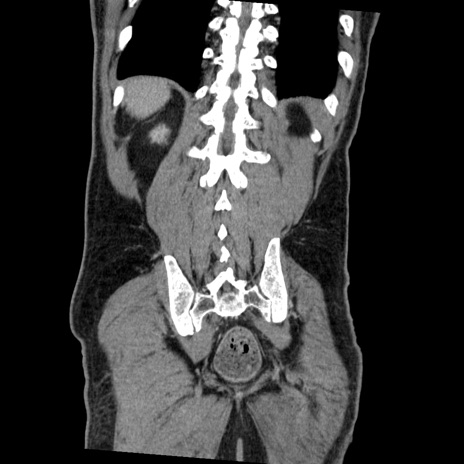

症例22(冠状断像)

【症例】50歳代男性

【主訴】腹痛

【現病歴】AVMからの被殻出血のため回復期リハ病棟入院中。 本日午後3時頃急に下腹部痛が出現した。

【既往歴】AVM、被殻出血、虫垂炎、高血圧

【身体所見】意識晴明、左半身不全麻痺、会話の理解は良好、36.5°C、腹部:膨隆、全体に板状硬、下腹部正中に圧痛点あり、反跳痛-、筋性防御不明、右下腹部にope scar

【データ】WBC 9400、CRP 0.06